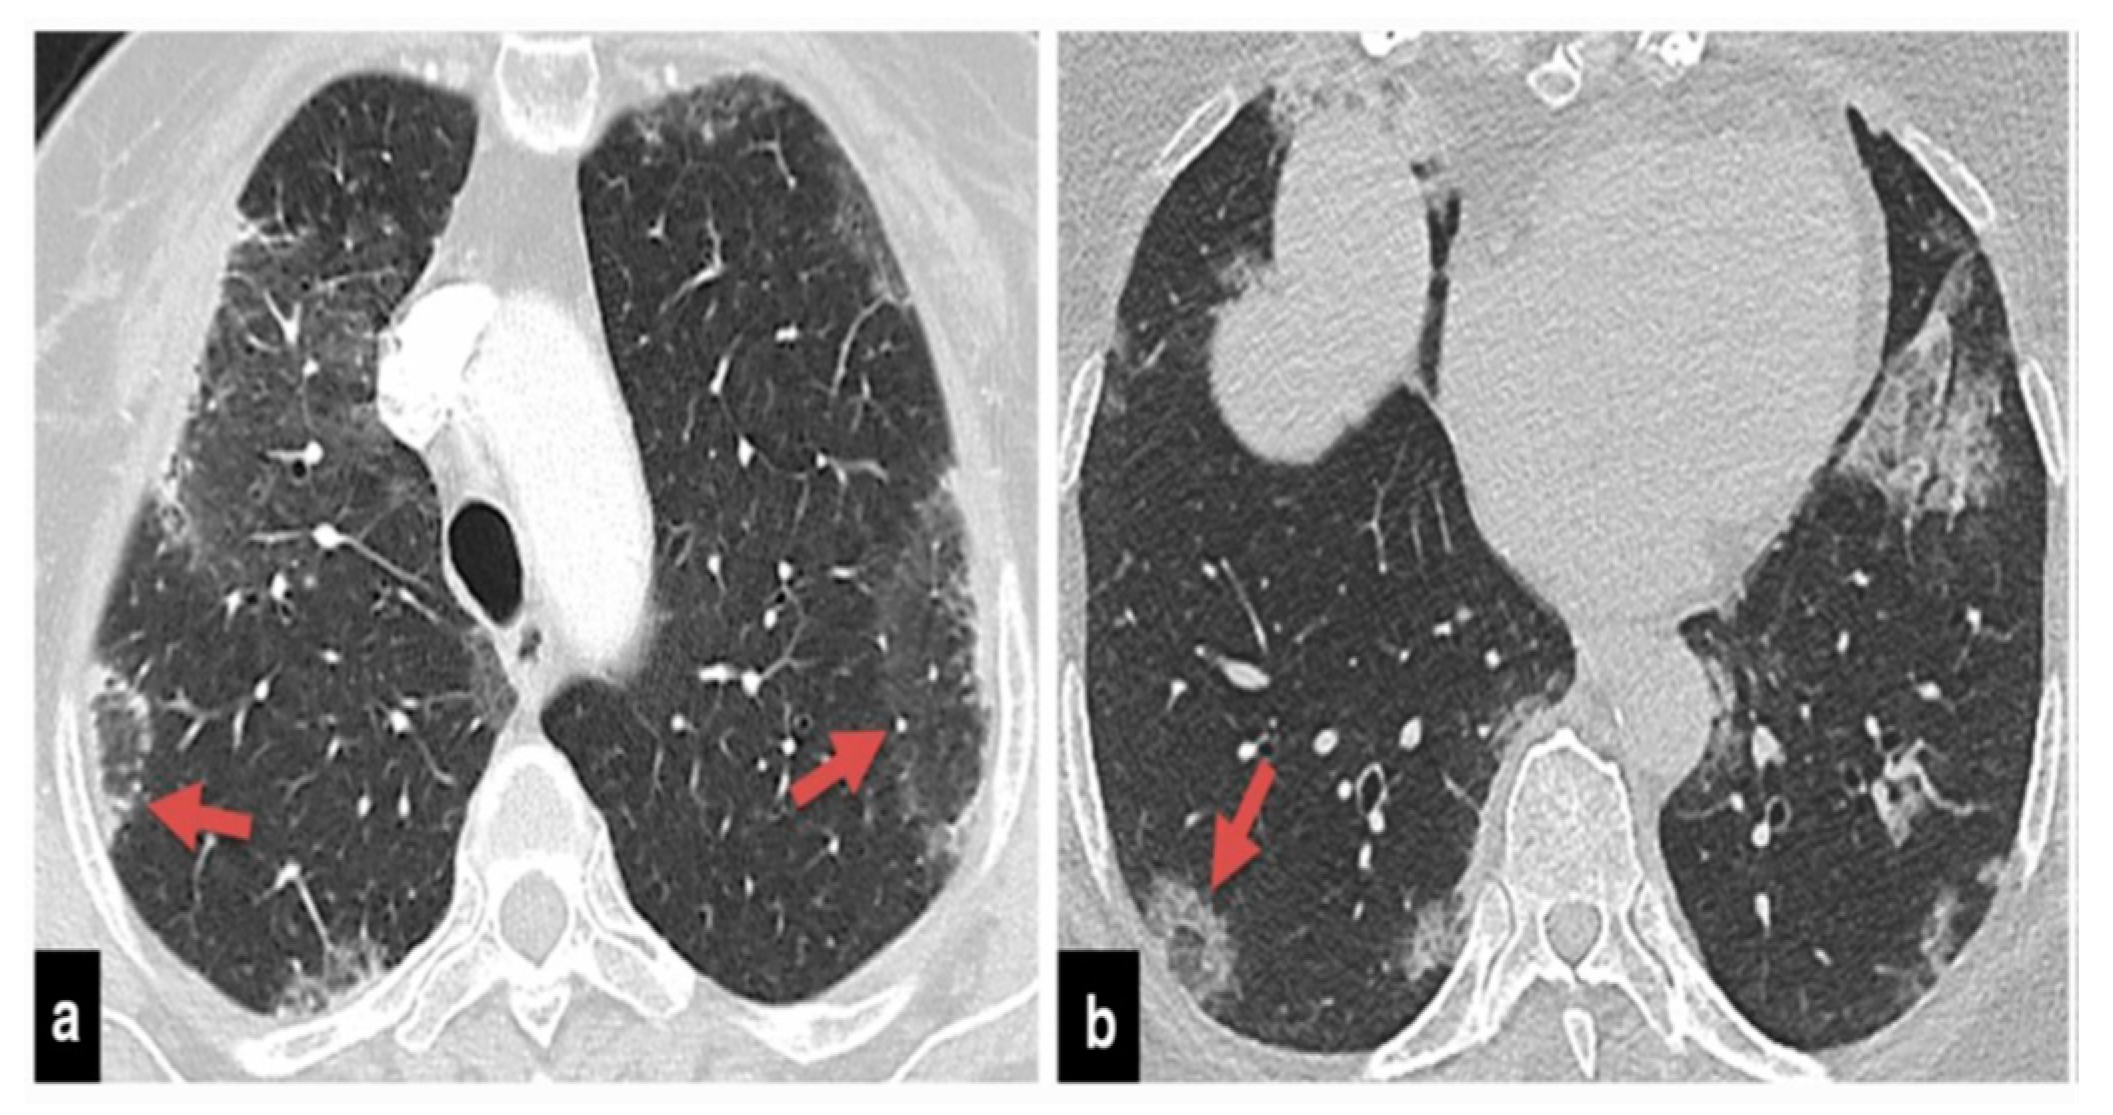

The precise contribution of pulmonary embolism (PE) to mortality in patients with SARS-CoV-2 remains uncertain due to the fact that not all patients routinely undergo CT pulmonary angiography and because there’s a limited number of autopsy studies available . However, in cases of patients suspected of having SARS-CoV-2 and exhibiting a strong clinical suspicion for PE, which can be determined based on symptoms like hemoptysis, unexplained rapid heart rate, or signs and symptoms of deep venous thrombosis alongside acute deterioration upon patient mobilization, it is advisable to consider performing CT pulmonary angiography (

Figure 1) .

Figure 2,

Figure 3 and

Figure 4) .